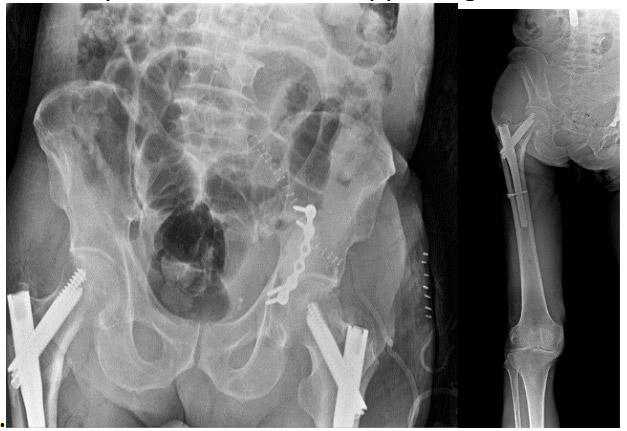

Post-surgery: X-ray shows bone cement and titanium plate in the left acetabulum, and fixation with nails in both thighs.